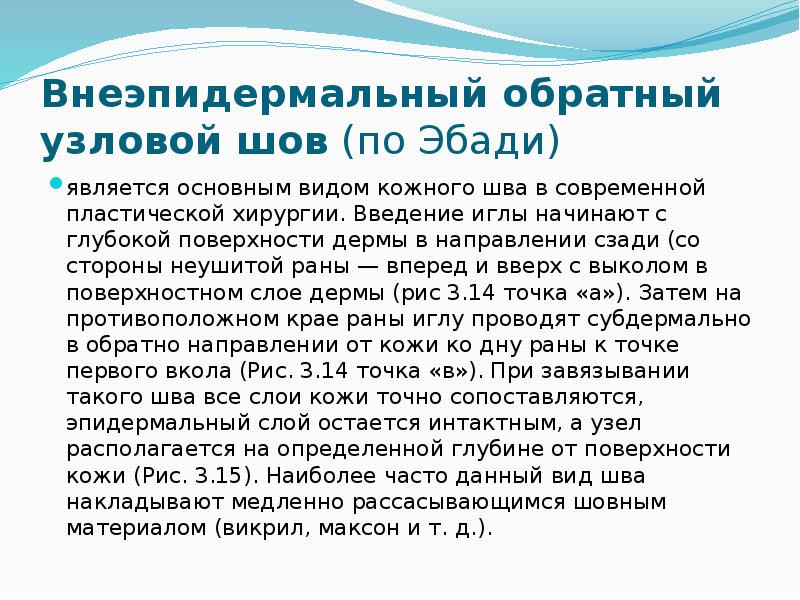

- 55. Внеэпидермальный обратный узловой шов (по Эбади) является основным видом кожного шва в современной